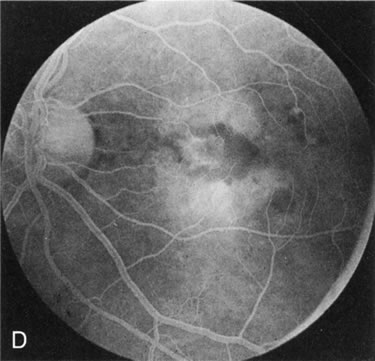

In the early stages of choroideremia, before choroidal atrophy is funduscopically obvious and when the picture resembles RP, FA indicates diffuse choroidal atrophy throughout the entire retina. Only the macular area remains preserved (Fig. 4A and B).

Fig. 4. Choroideremia and choroideremia carrier. A. The choroidal atrophy in this affected male is not apparent in the fundus. B. However, the angiogram shows diffuse atrophy of the choriocapillaris with persistent visualization of the larger choroidal vessels. C. This carrier female has peripapillary choroidal atrophy and diffuse pigment mottling. D. The patchy areas of focal choroidal atrophy that occasionally occurs in carriers is evident on angiography.

The typical carrier female, with focal or diffuse pigment mottling, does not show choroidal atrophy. However, a few carrier females have a more severe form with focal areas of choroidal atrophy. The presence of these areas, and possible progression, can be documented by FA (Fig. 4C and D). These carriers exhibit a mosaicism, which is explained by the Lyon hypothesis of random X-chromosome inactivation.